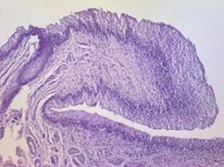

- Digestive System